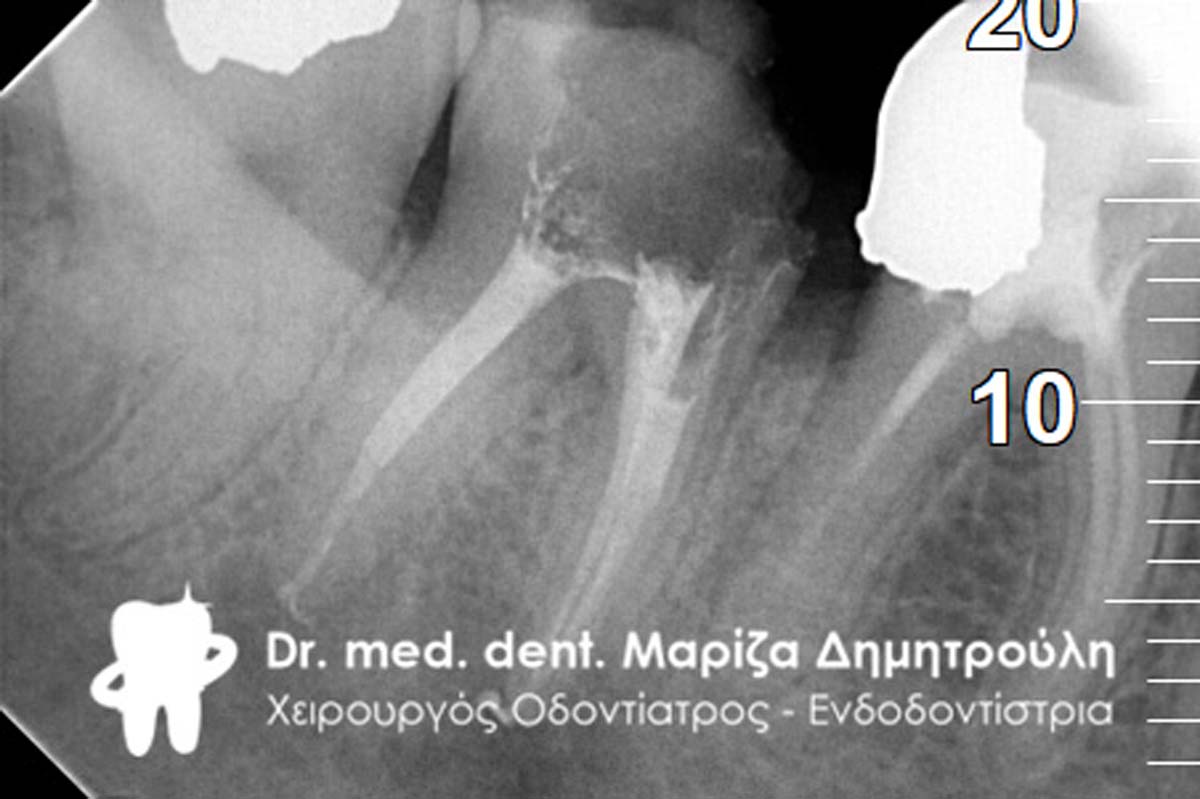

Ο ασθενής είχε έντονο απόστημα στη δεξιά πλευρά της κάτω γνάθου, καθώς απέφευγε να θεραπεύσει το συγκεκριμένο δόντι τον τελευταίο ένα χρόνο. Αιτία του αποστήματος αυτού ήταν η αποτυχία μιας παλιάς απονεύρωσης που είχε στον πρώτο γομφίο της κάτω γνάθου. Μετά από συνεννόηση με τον ασθενή αποφασίστηκε η επανάληψη της απονεύρωσης, καθώς ο ασθενής επιθυμούσε τη διατήρηση του δοντιού στο στόμα του. Κατά τη διάνοιξη του δοντιού εντοπίστηκε και τέταρτος ριζικός σωλήνας, ο οποίος δεν είχε εντοπιστεί και καθαριστεί στην πρώτη απονεύρωση του δοντιού και ίσως να είναι και η αιτία φλεγμονής του δοντιού. Οι φωτογραφίες δείχνουν την εικόνα του δοντιού μετά την αφαίρεση της παλιάς απονεύρωσης, την νέα επεξεργασία και την ικανοποιητική διάνοιξη των ριζικών σωλήνων. Είναι σημαντικό σε μία απονεύρωση οι ριζικοί σωλήνες να διανοίγονται επαρκώς, ώστε να απομακρύνονται όσο το δυνατόν καλύτερα τα μικρόβια και οι μολυσμένοι οδοντικοί ιστοί από το εσωτερικό των ριζών του δοντιού όπως επίσης να υπάρχει επαρκής χώρος για να εισέρχονται και να δρουν ικανοποιητικά τα απολυμαντικά διαλύματα.

Μετά την ολοκλήρωση της θεραπείας ο ασθενής δεν πονάει πλέον και αισθάνεται πολύ καλά.

ΠΡΙΝ

ΜΕΤΑ

ΜΕΤΑ- Προσπάθεια λήψης ακτινογραφίας του 4ου ριζικού σωλήνα του δοντιού

ΠΡΙΝ- Εικόνα του αποστήματος